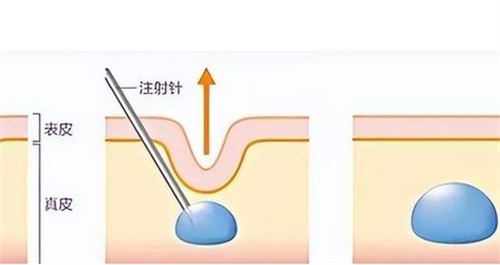

微晶瓷注射了山根怎么取出?微晶瓷山根取出解析:适用情况|操作流程|注意事项全揭秘

微晶瓷注射了山根怎么取出?微晶瓷山根取出解析:适用情况|操作流程|注意事项全揭秘微晶瓷注射了山根怎么取出是不少做过微晶瓷隆鼻人群关心的问题。很多人在微晶瓷注射山根后,可能因为结果不理想、出现不良反应等原因,想要取出微晶瓷,却又不知道该怎么做,十分苦恼